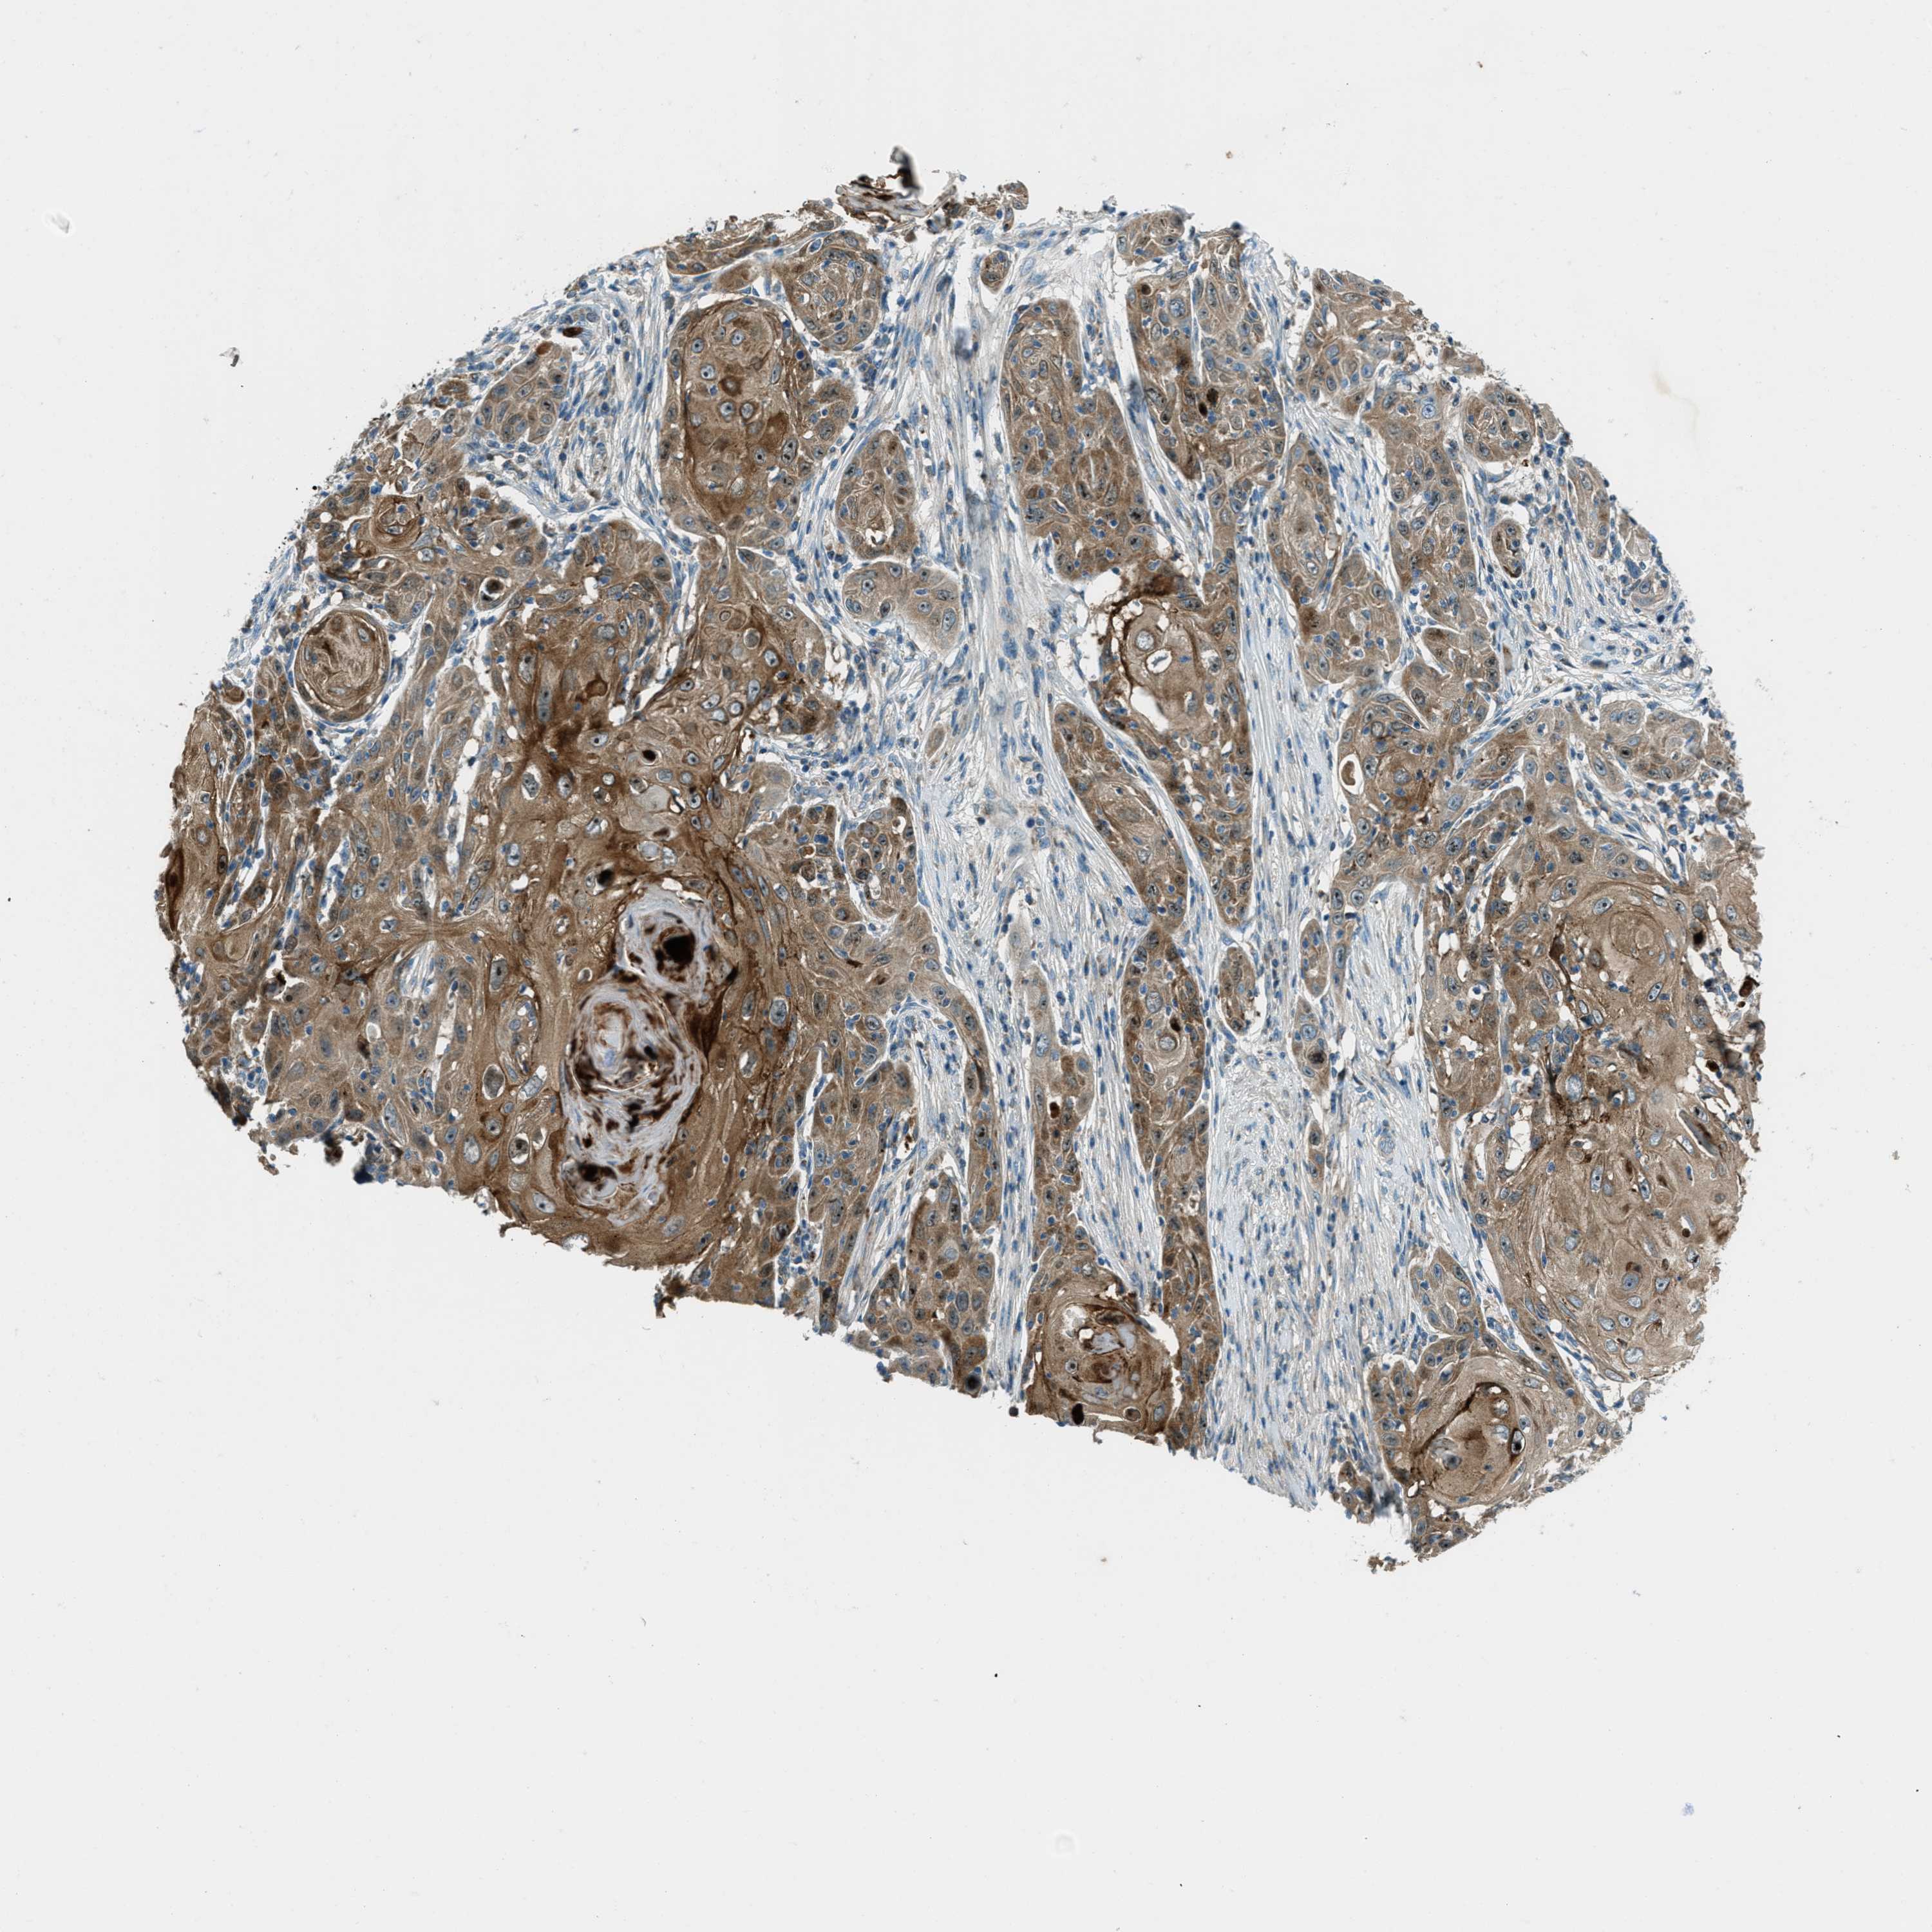

SKIN CANCER - Protein expressioni

A mouse-over function shows sample information and annotation data. Click on an image to view it in a full screen mode. Samples can be filtered based on level of antibody staining by selecting one or several of the following categories: high, medium, low and not detected. The assay and annotation is described here.

Antibody stainingi

Antibody staining in the annotated cell types in the current human tissue is reported as not detected, low, medium, or high, based on conventional immunohistochemistry profiling in selected tissues. This score is based on the combination of the staining intensity and fraction of stained cells.

Each image is clickable and will lead to virtual microscopy that enables deeper exploration of all samples and also displays staining intensity scores, fraction scores and subcellular localization as well as patient and tissue information for each sample.

Antibody HPA017322

Staining

High

Medium

Low

Not detected

Intensity

Strong

Moderate

Weak

Negative

Quantity

>75%

75%-25%

<25%

None

Location

Nuclear

Cytoplasmic/membranous

Cytoplasmic/membranous,nuclear

Squamous cell carcinoma, NOS